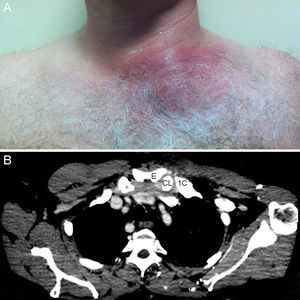

Case 4. Male 75 years, allergic to beta-lactams, diagnosed with actinic proctitis. He consulted for rectal bleeding, fever of 39° C and pain in the cervical region for 2 days. In the ER he developed erythema and edema, as well as pain on palpation of the anterior cervical region. A cervical CT angiography determined swelling of the sternoclavicular joint and the sternocleidomastoid, with protrusion into the premediastinic space (Fig. 1) contacting the brachiocephalic vein. In the SF, Staphylococcus aureus was isolated.